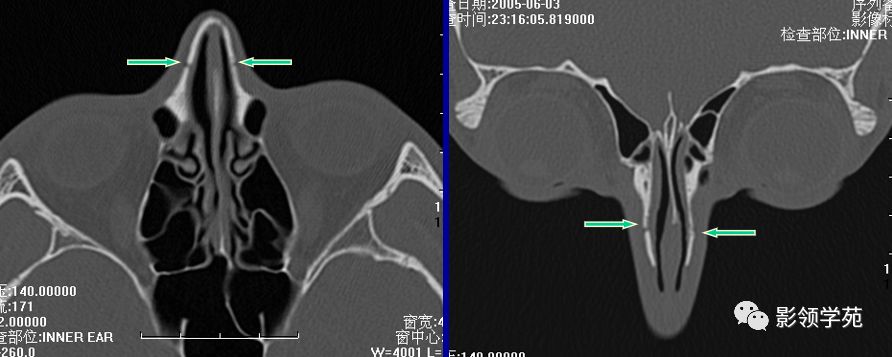

线性骨折 粉碎骨折

右侧鼻骨线形骨折

鼻骨线形骨折

左侧鼻骨线形骨折